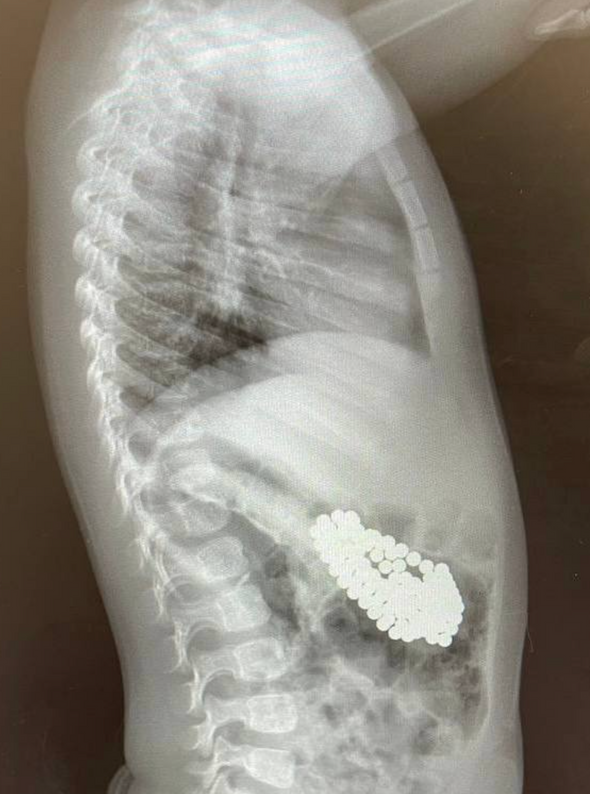

Врачи спасли полуторагодовалого ребенка, проглотившего 130 магнитных шариков и литиевую батарейку

Врачи клиники имени Рошаля извлекли из ЖКТ полуторагодовалого мальчика порядка 130 магнитных шариков и литиевую батарейку. Об этом сообщается на сайте минздрава Московской области.

В Детский клинический центр имени Рошаля поступил ребенок с подозрением на проглатывание инородных тел. Обследование выявило в желудке полуторагодовалого мальчика скопление большого количества магнитов и батарейку. Инородные тела необходимо было извлечь как можно быстрее, так как магниты и батарейки при соприкосновении со слизистой в организме очень быстро окисляются, что приводит к внутренним ожогам, перфорации внутренних органов, некрозу тканей и кровотечению.

Врачи рассказали, что с помощью специальных инструментов — эндоскопического «Сачка», зажима по типу «Аллигатор» и «Корзины Дормиа» провели гастроскопию. В ходе процедуры хирурги последовательно извлекли из желудка мальчика 130 магнитов и литиевую батарейку. Магниты сцепились друг с другом, что привело к повреждению слизистой оболочки и образованию язвы.

После эндоскопии врачей ждал неприятный сюрприз, так как на послеоперационном рентгене они обнаружили еще три магнита, которые невозможно было удалить с помощью эндоскопа. Ребенок, по всей видимости, глотал магниты в разное время, поэтому некоторые из них уже переместились в кишечник. Находясь там, они сцепились и притянули друг к другу желудок и кишечник. Извлечь опасные предметы можно было только хирургическим путем.

снимки: mz.mosreg.ru